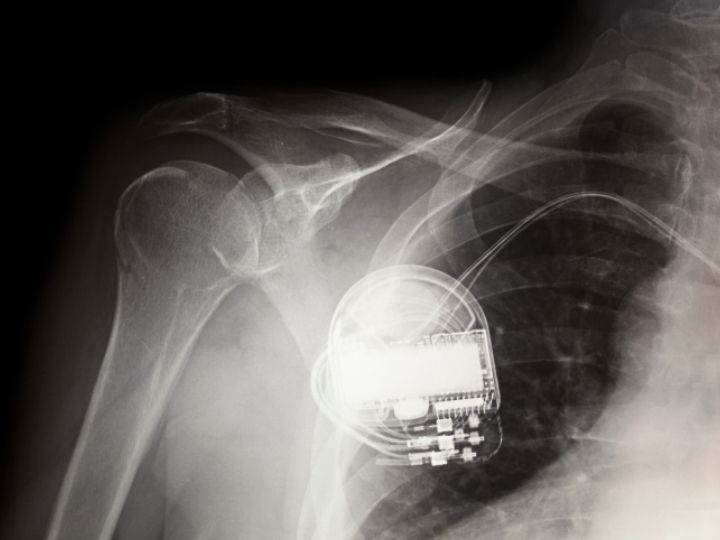

Pacemakers implanted in human hearts and utilizing lithium batteries could instead be self-powered as natural movement generates electrical power.

The potential uses are profound. Human-like robots made with soft-elastomers that contain increased flexoelectric properties would be capable of a greater range of motion to perform physical tasks. Pacemakers implanted in human hearts and utilizing lithium batteries could instead be self-powered as natural movement generates electrical power.